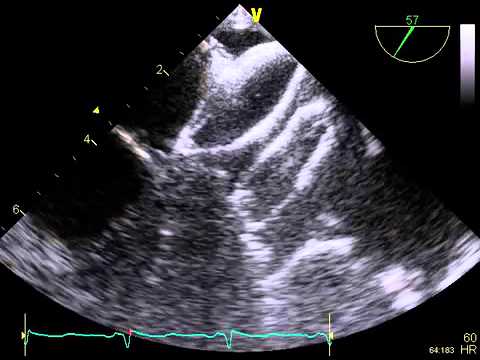

Video 7.2

Video 7.2 Tenting of the atrial septum seen with the transseptal needle.